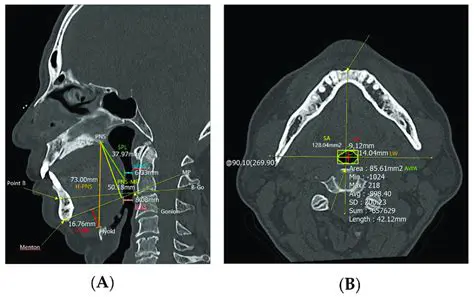

Efficient Cephalometric Analysis